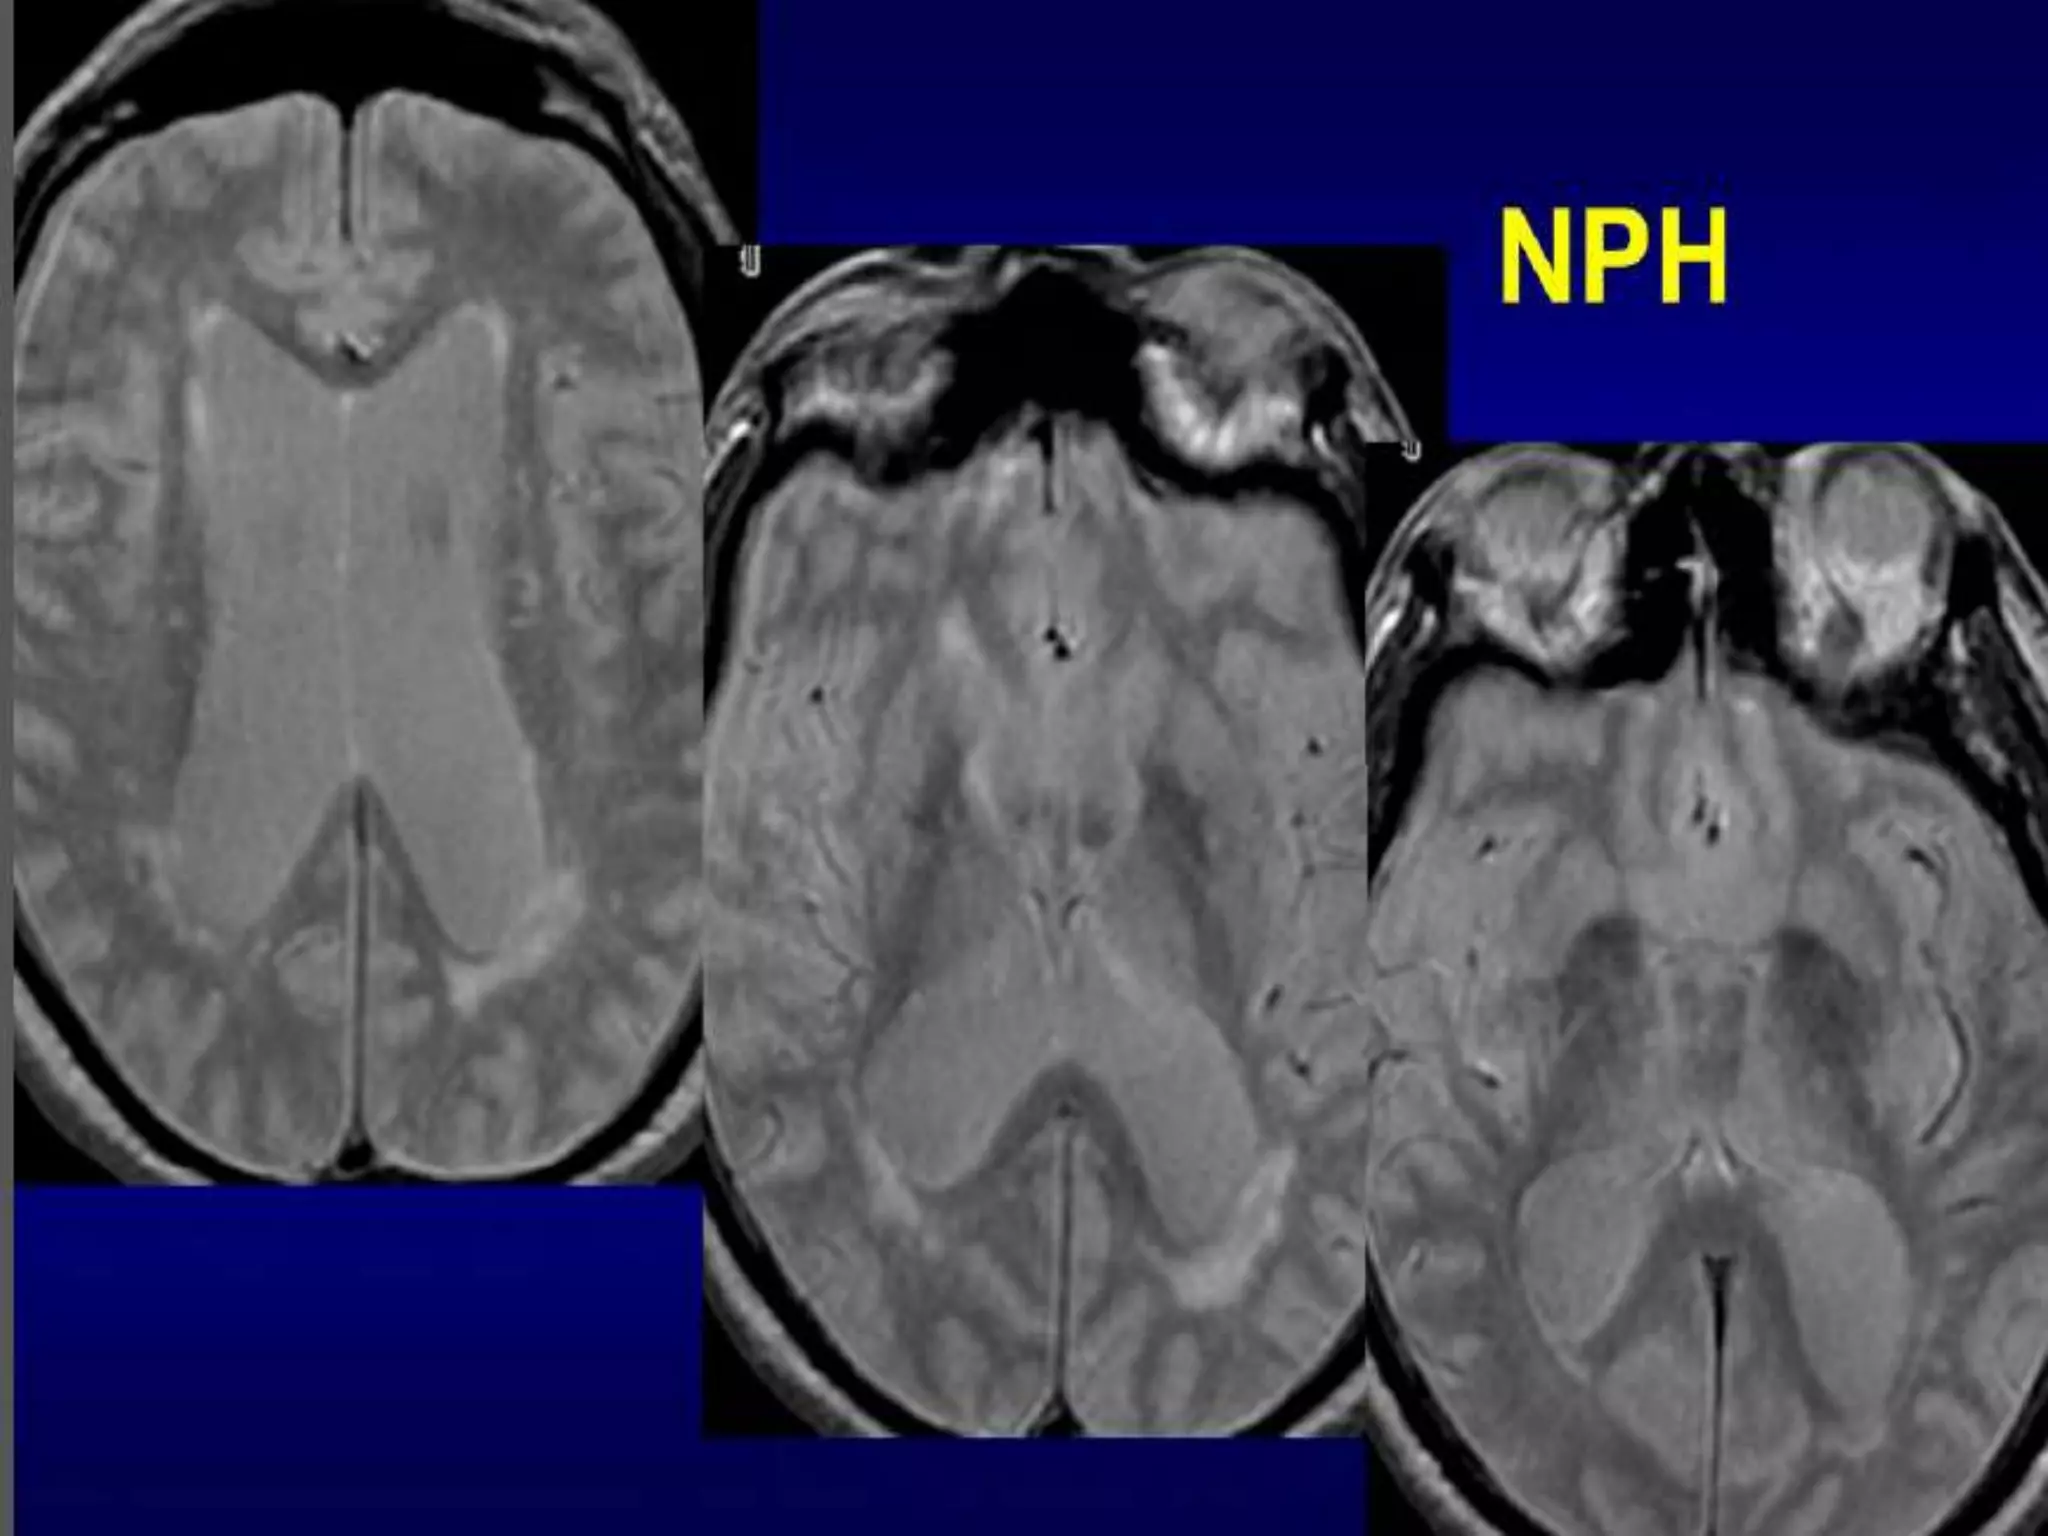

NPH.